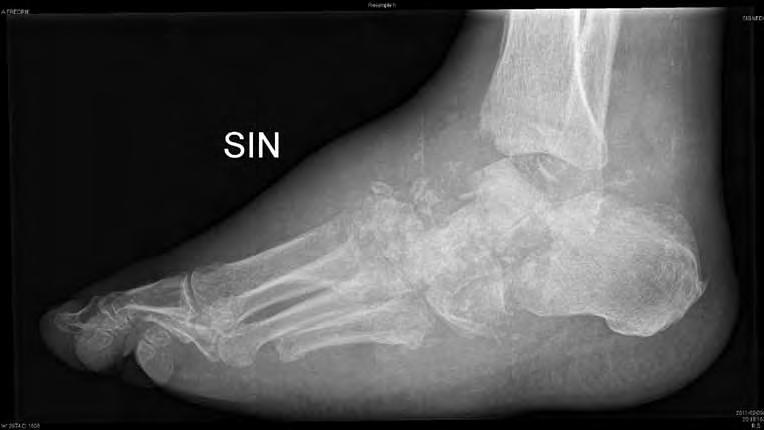

Typ III Bakfot med talus, subtalar- och NCleder (Figur 2)

Bakfotscharcot leder oftare till instabilitet och karaktäriseras oftare av destruktiva benförändringar. Bakfoten kan bli breddökad och felställd.

Fotledscharcot leder också ofta till instabilitet och grava felställningar med stor risk för sår och osteit.

4) En instabil och icke belastningsbar fotled behöver stabiliseras medelst artrodes i syfte att förebygga amputation (Figur 6a-d).